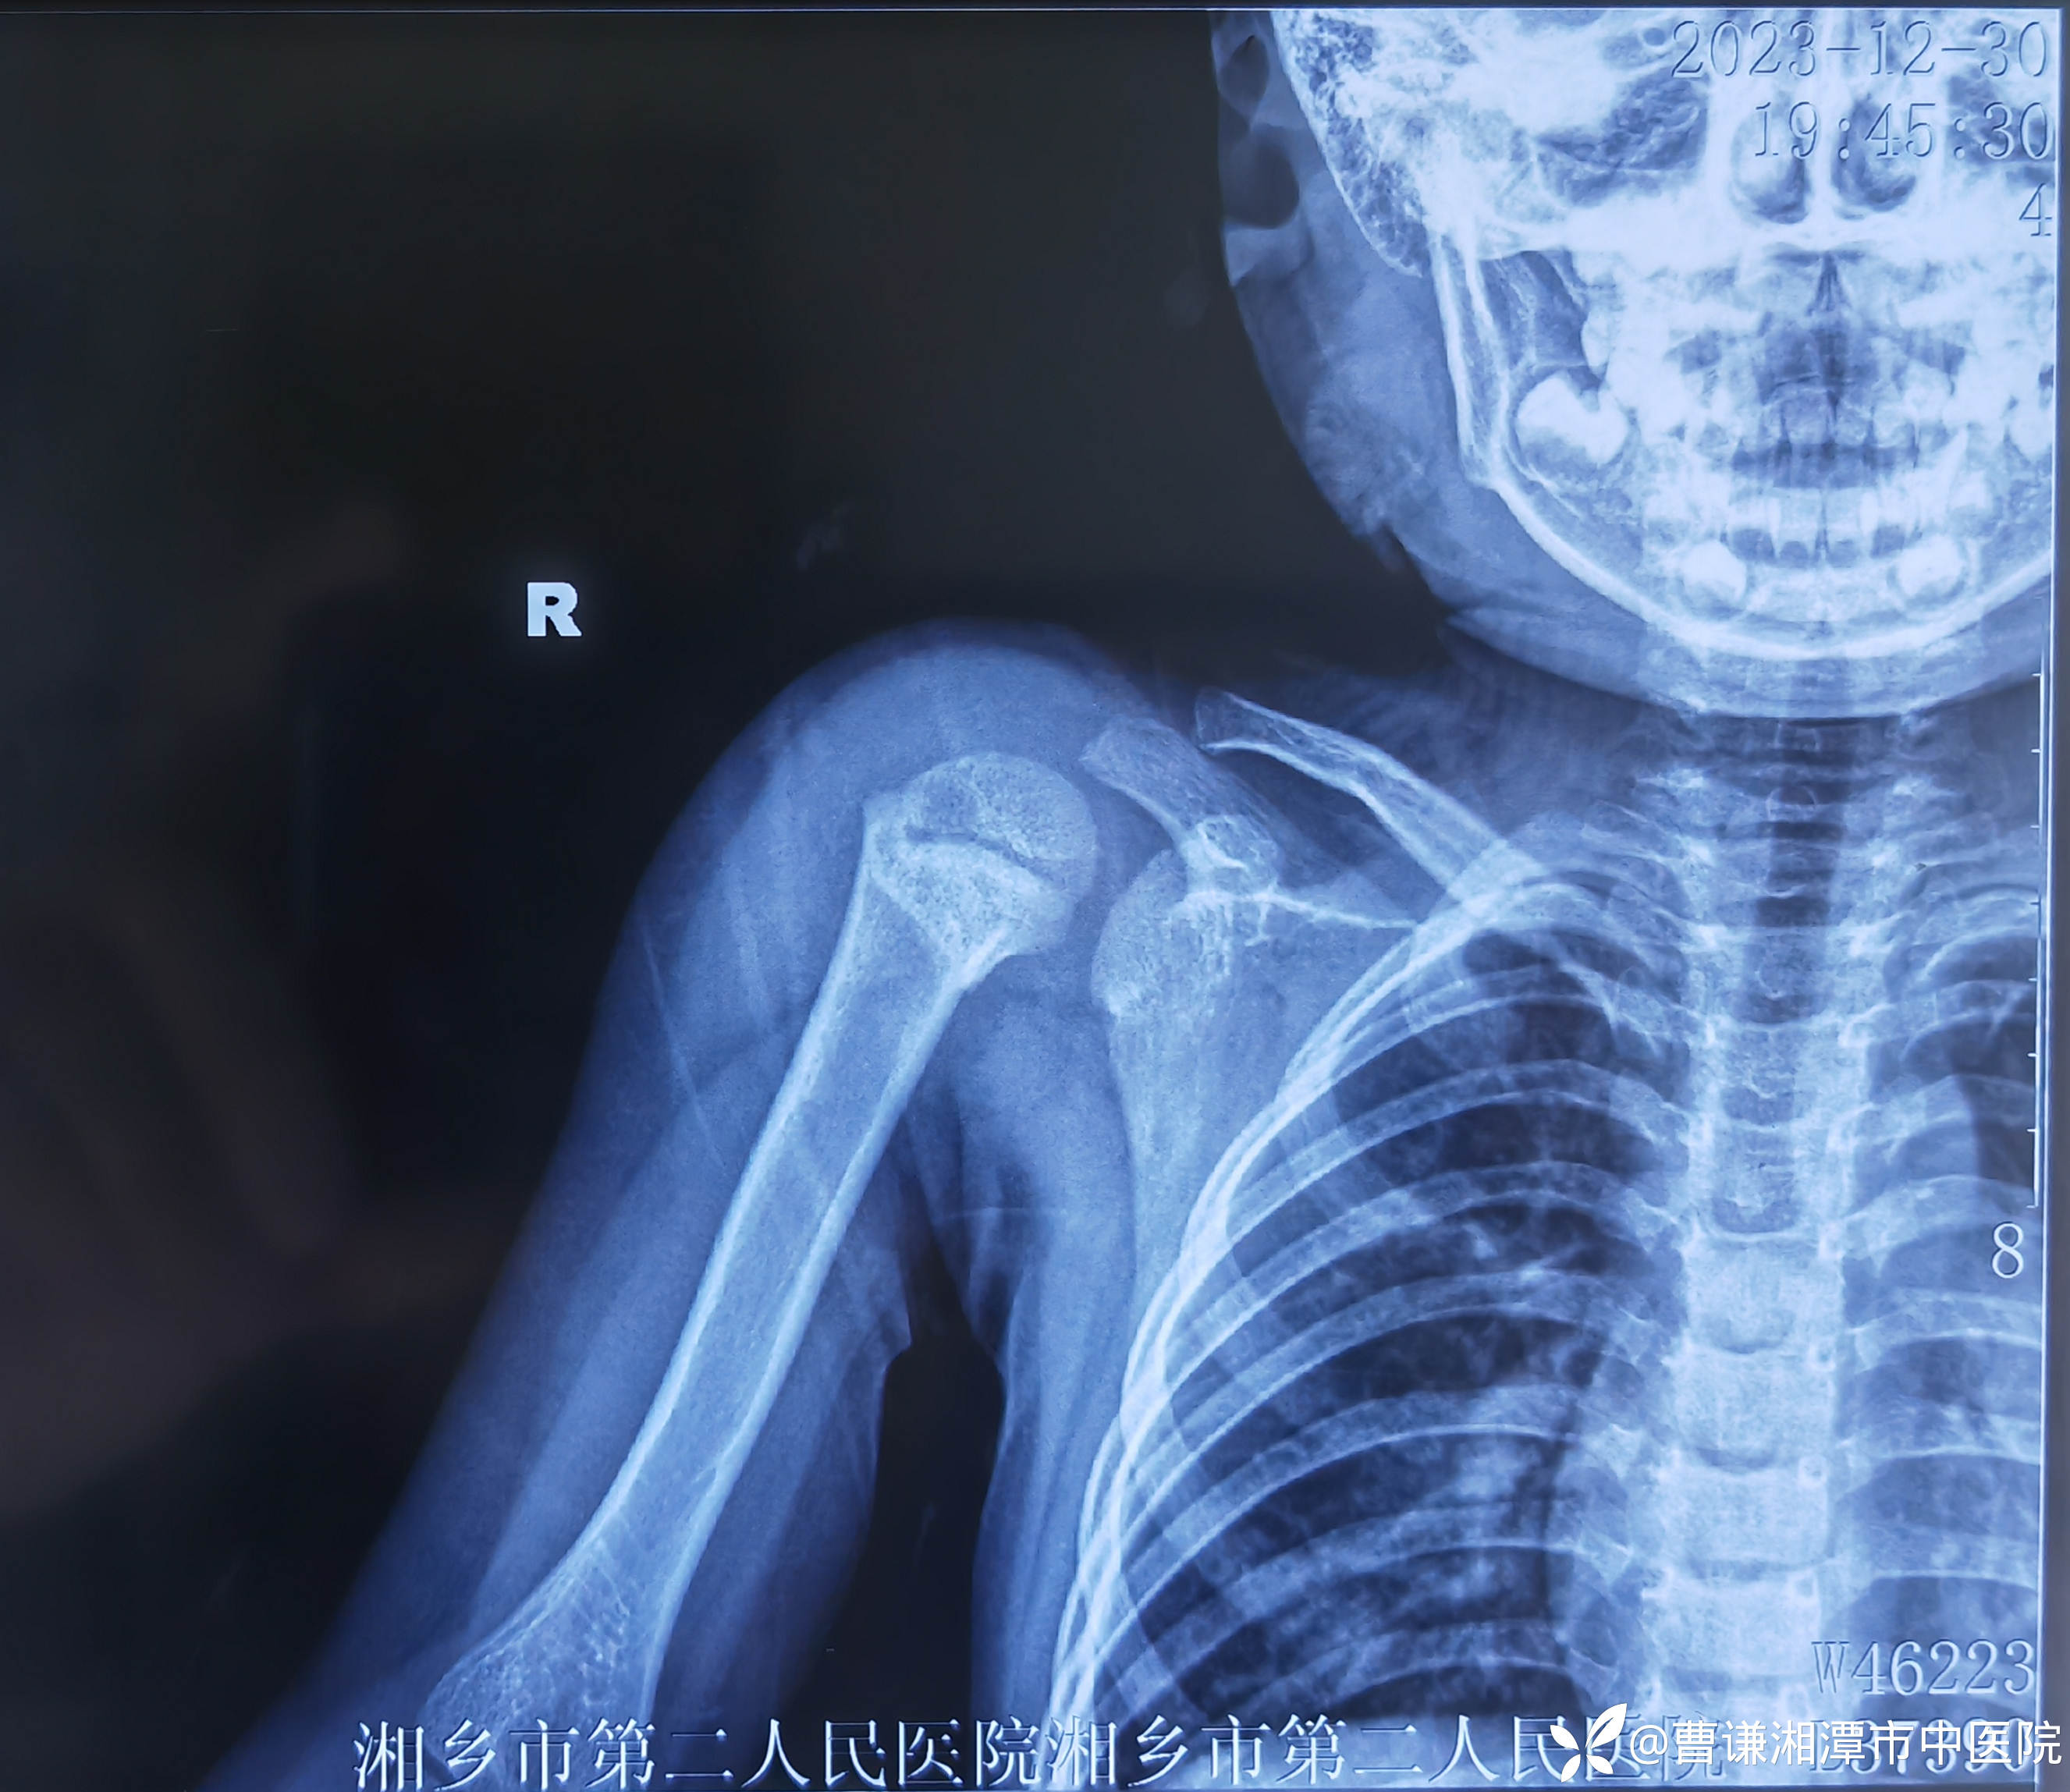

辅助检查:X线片:右肱骨近端骨折,断端错位明显。

患者跌倒致右肩部肿痛,活动受限,就诊于当地医院,拍片示右肱骨近端骨折,初看片子似乎骨折对位良好,其实仔细看可以发现断端重叠明显,虽然拍了两个片子,但其实都是正位,当地医院建议手术治疗,患者家属拒绝手术治疗,转来我院要求保守治疗。